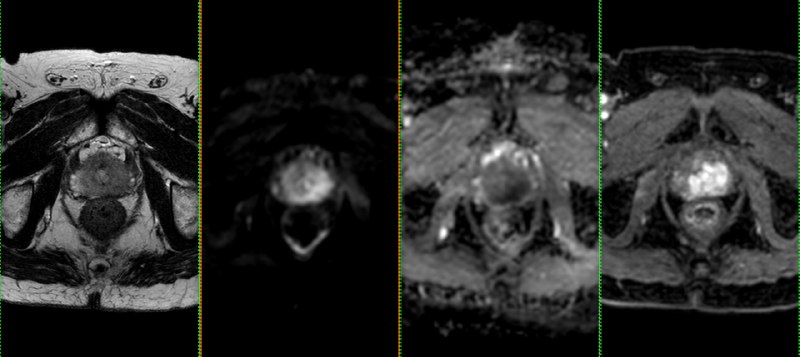

Всем привет!

А вот для чего иногда нужен контраст на МРТ предстательной железы: по DWI, а она является основной последовательностью для оценки периферической зоны, типичные изменения ПИРАЦ-4 (наибольший размер - 12 мм), но вот на Т2 - жидкость, а не серость, и на постконтрастных накопления контраста нет вообще. Так что, это - абсцесс, а не рак.

Соблюдайте протокол и не будете разочарованы.